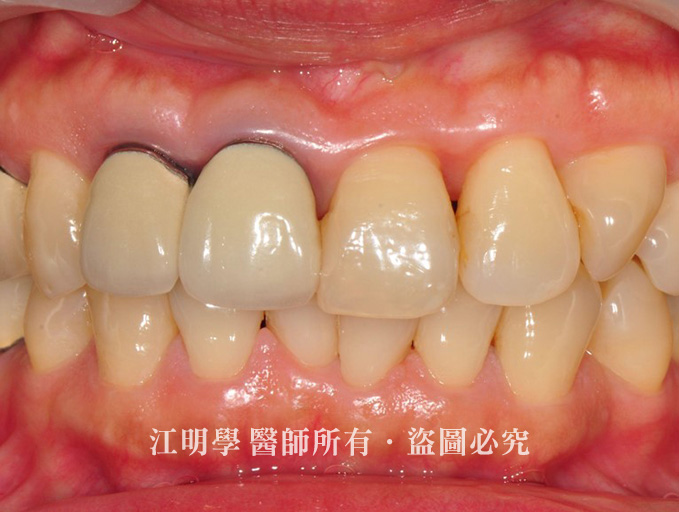

金屬假牙造成牙齦黑邊

治療前:金屬邊外露,假牙周圍呈現黑色。